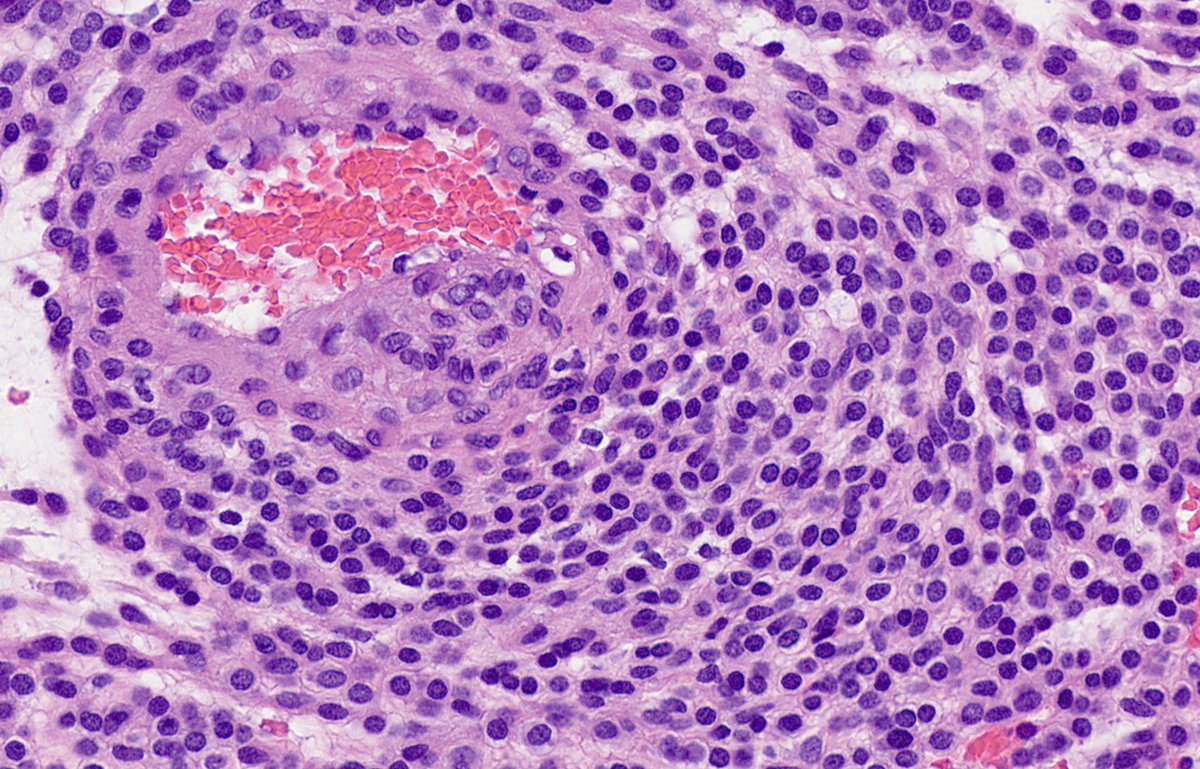

Thanks to all who engaged! Although uncommon, chronic LCH can lead to severe secondary pulmonary HTN which is what we see here. A spectrum of arterial lesions, including plexiform, dilatation, and medial hypertrophy. Wishing the patient a new lease on life with new lungs!

Explants from woman in her mid 40s. Clinical history on req: pulmonary hypertension. IHC is CD1a. Unifying diagnosis?

!